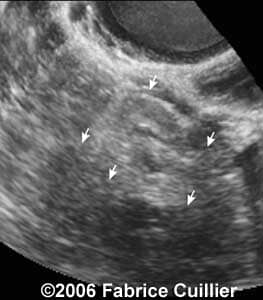

These are some cases of ectopic pregnancy (GEU) using the 2D and 3D scans.

Case 1